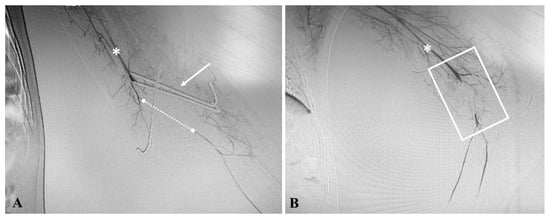

3.3. Institutional Case Report #3—Aortic Injury and Open Surgery for Failed Endovascular Treatment